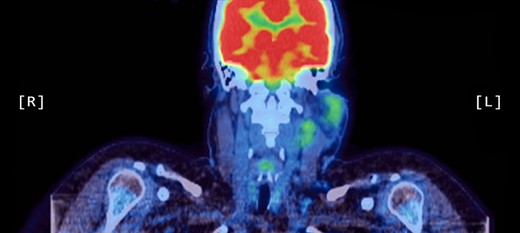

A computed tomography (CT) scan demonstrated left parotid multifocal soft tissue abnormality and enlarged left-sided cervical lymph nodes, with prominent superficial left supraclavicular fossa lymph nodes (Figs 3 and 4).

Coronal CT sinuses (with contrast) showing left parotid multifocal soft tissue abnormality (A) with enlarged left-sided cervical and superficial supraclavicular fossa lymph nodes (B).